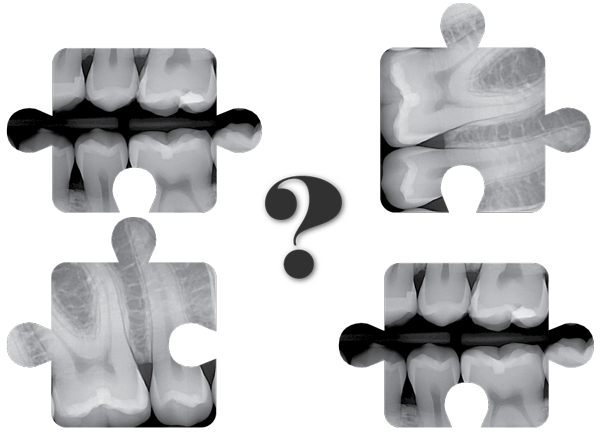

Will DentiMax Dental Sensors Work in Eaglesoft ®/ Patterson ® Imaging?

How DentiMax' dental sensors work when it comes to capturing dental xrays in Eaglesoft.